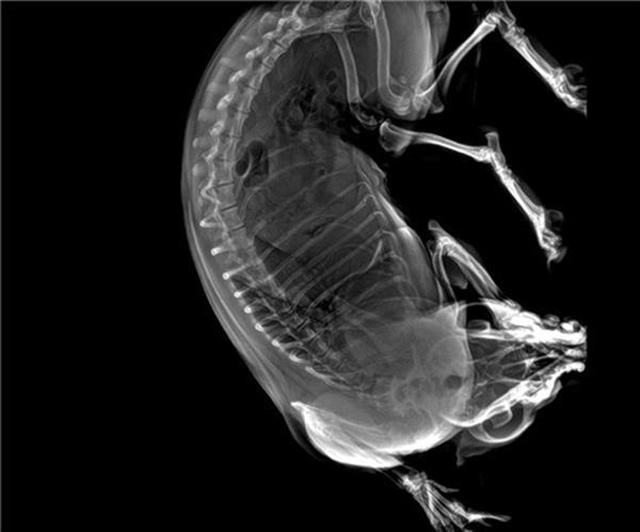

寵物DR的工作原理是X光線(xiàn)穿透動(dòng)物體后在屏幕或者膠片上面顯示體內(nèi)影像。輔助寵物醫(yī)生讀片跟準(zhǔn)確的治療,寵物DR顯示是寵物醫(yī)院診所的配置,提高了診斷的效率。DR的檢測(cè)效率比X線(xiàn)高44%,成像快采集時(shí)間10MS以下。3秒左右就可以看到檢查圖像。常規(guī)的胸部DR還要幾分鐘。所以寵物DR的出片速度是非??斓?。很高的空間分辨率低噪音??梢垣@得高清圖像,提高檢測(cè)正確率避免誤診等等問(wèn)題。數(shù)字化圖像的優(yōu)勢(shì)是可以保留原始數(shù)據(jù),圖片識(shí)別,二三維的重建,醫(yī)學(xué)影像學(xué)實(shí)現(xiàn)全數(shù)字化和無(wú)膠片化鋪平了道路。提供照片打印服務(wù),防止照片丟失而重復(fù)照片。有針對(duì)性的對(duì)圖像進(jìn)行處理,以提高診斷率。寵物DR的輻射量很低的,對(duì)人體的輻射風(fēng)險(xiǎn)不大。